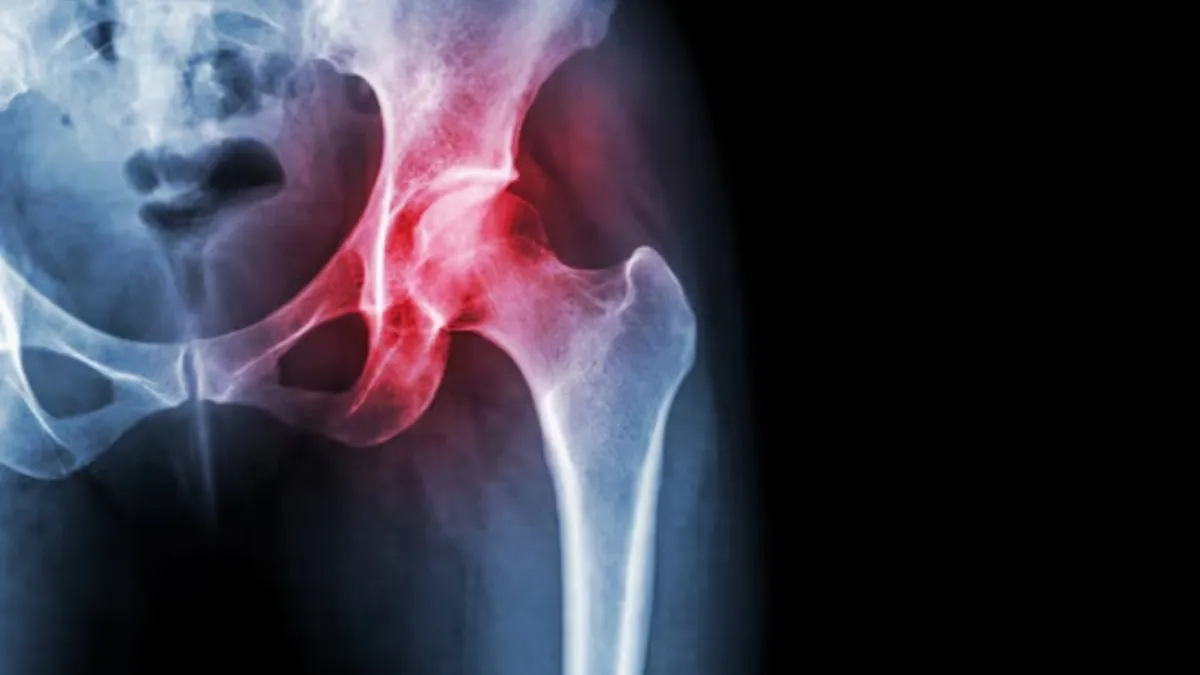

Know the types, causes and treatment of hip arthritis.

Know the types, causes and treatment of hip arthritis. Image Source : Freepik

Hip arthritis tends to manifest in various forms, each with different characteristics and underlying causes. Hip arthritis means the deterioration of the cartilage of the hip joint. It can create challenges for one who is grappling with this form of arthritis. Here are different types of hip arthritis that one should be aware of. One should seek timely intervention to improve the quality of life.

Osteoarthritis of the hip: This is the most common form of arthritis, and the hip is the second most frequently impacted joint, according to Dr Aashish Arbat, Orthopedic & Joint Replacement Surgeon, Jehangir Multispeciality Hospitals, Pune. Osteoarthritis will cause wear and tear of the cartilage, as a result, it becomes thinner and the surfaces of the joint tend to get rougher. The symptoms of this type of arthritis are swelling, pain, and stiffness, but not everyone will have these symptoms. The causes of this arthritis are family history, obesity, hip injury, hip joint problems, age, and repetitive activities leading to hip pain. The treatment of it is exercise, weight loss, physical therapy, medication, and rest. Surgical treatment includes a total hip replacement (arthroplasty) wherein the damaged hip socket and the head of the femur are removed and replaced with implants made with the help of metal, plastic, ceramic, or some combination. This minimally invasive surgery offers relief from hip pain, is safe, and aids in the swift recovery of the patient.